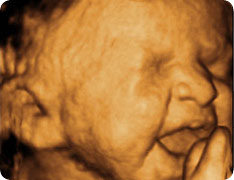

Плод в утробе умеет кричать и плакать! Американские ученные с помощью 4d УЗИ исследовали мимику плода — малыш шевелится, сдвигает бровки, сморщивает личико, а щечки начинают мелко дрожать, при этом он тяжело вдыхает и выдыхает, высовывает язычок и сглатывает.

Подобная «плакательная» лицевая мимика была неожиданно замечена и зафиксирована в результате исследования последствий употребления матерью алкоголя, курения и наркотиков. При этом наблюдались плоды, старше 28-ми недель, а «плакательная» реакция намеренно вызывалась путем безвредных виброакустических воздействий на плод.

Открытие лицевой мимики у плода согласуется с концепцией о том, что плод имеет эмоциональную память с 18-недели беременности.